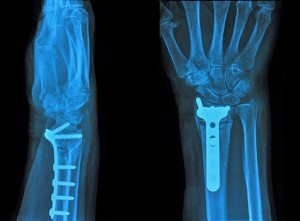

Occasionally (given the severity of the fracture), the bones must be surgically fixated. This will ensure the bones are placed in their proper placement. The most common surgeries for fractures are manipulation (reduced), closed reduction and open reduction.

Fractures do not heal overnight. Your doctor will obtain radiographs (x-rays) of the fracture site to ensure there is healing. Usually around 6 weeks you will begin to see callus formation (bone healing), and most of the time at 12 weeks the fracture is healed.